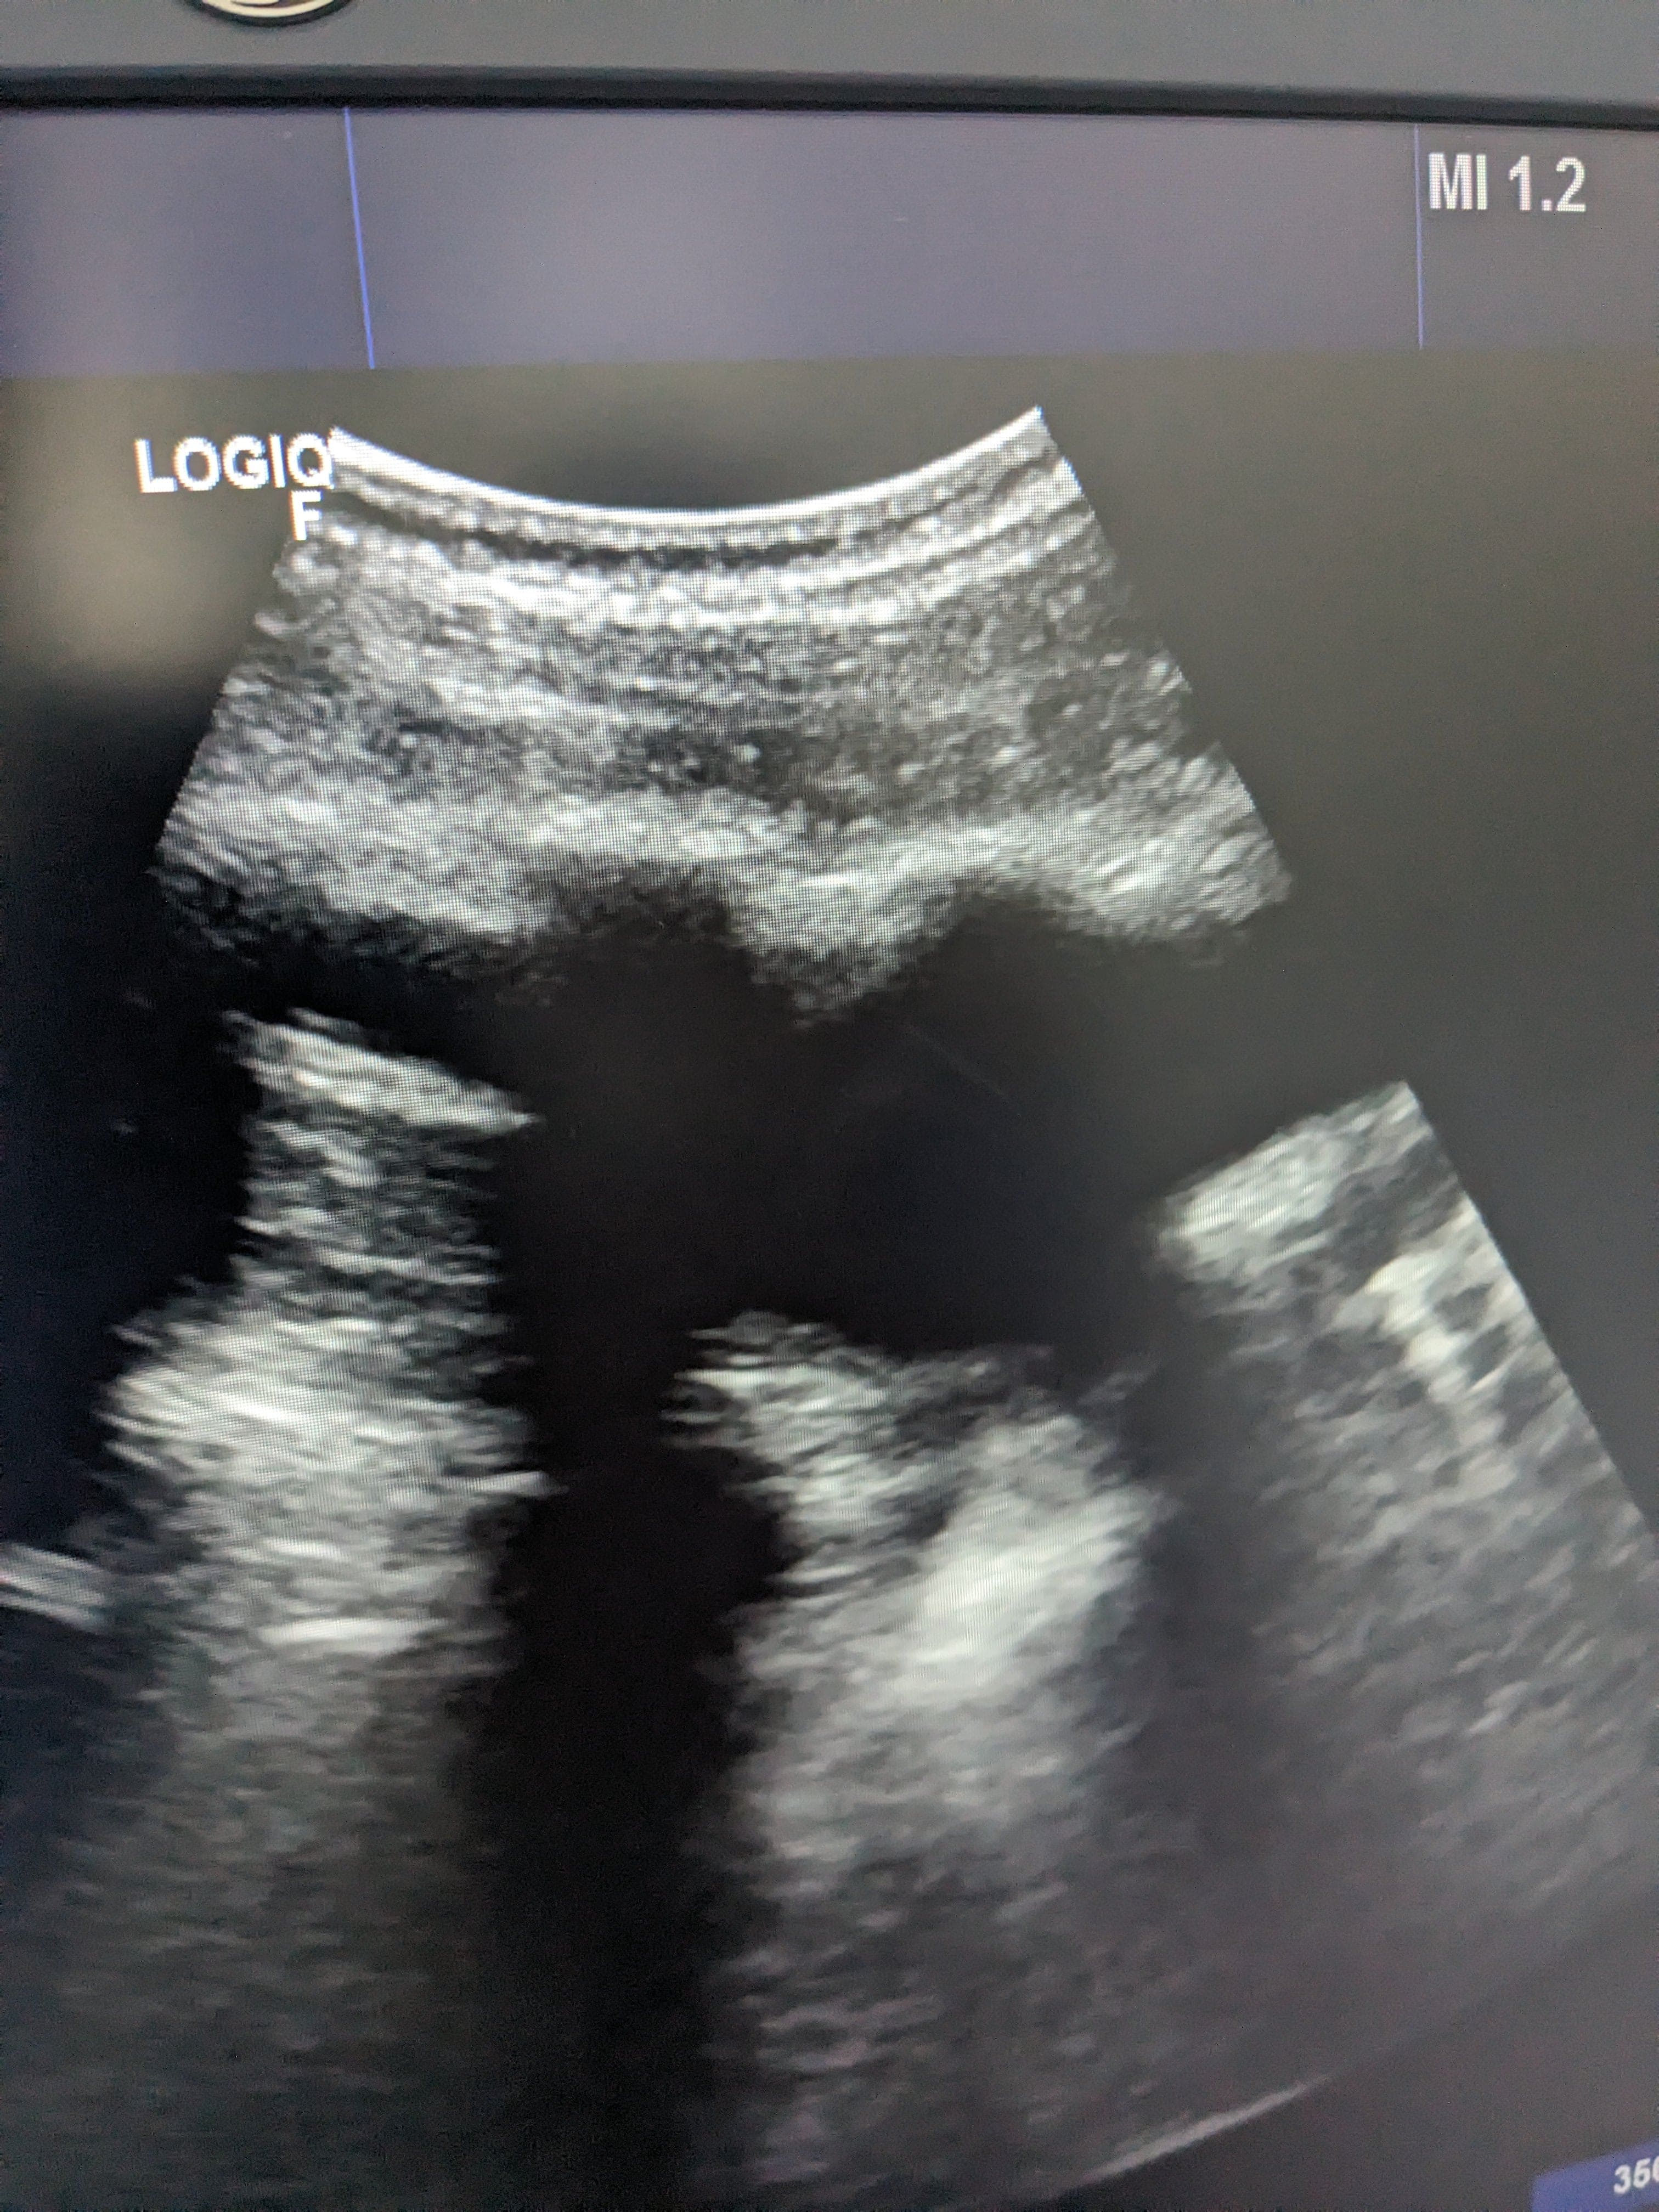

Se hace ecografía clinica en la consulta de atención primaria, observamos derrame pleural en pulmón izquierdo hasta medio campo pulmonar.